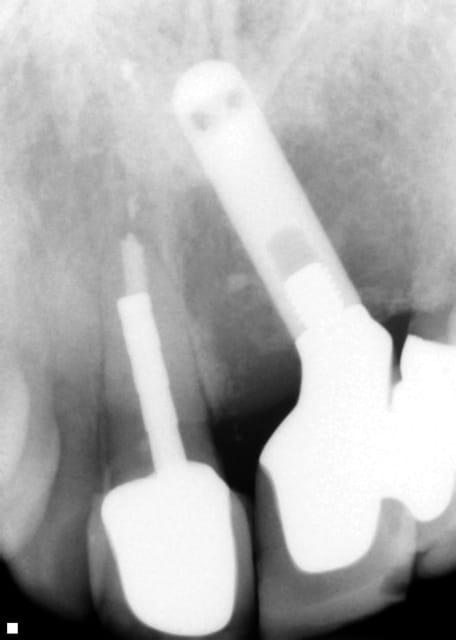

Tiens, dans le sujet, consultation cette semaine...

Alors, on fait quoi ?

Poche de 12 ++ mm sur la 21

Pus en quantité +++

Énorme lésion

Mobilité de la 23 (un peu)

Mobilité de la 11 aussi.

Alors ?

maintenant, je suis de l'avis de flicflac, il s'agit probablement d'un implant IMZ recouvert d'hydroxyapatite (=surface rugueuse/poreuse) probablement impossible à décontaminer...

C'est un IMZ : irrécupérable quelle que soit la technique.

L'IMZ était recouvert de plasma spray de Titane, pas de série avec de l'hydroxyapatite je pense. Mais impossible à décontaminer quand même et des arrachements possibles du plasma spray du corps de l'implant qui ne présentera donc plus à ces endroits de possibilité d'ostéointégration.